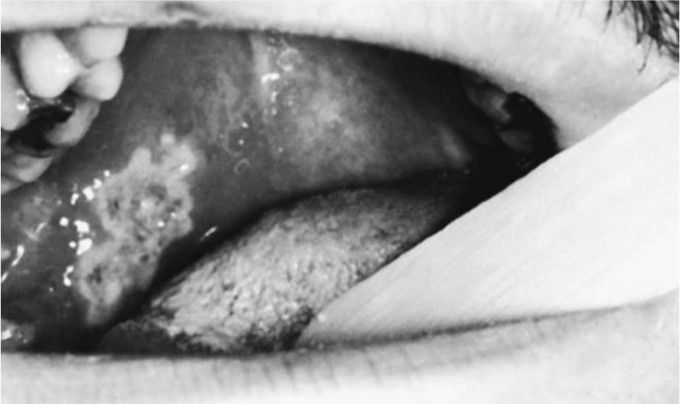

Palate ulceration

Palatal ulceration in a 21-year-old male with fusospirochetal stomatitis, which began as a necrotizing lesion of a pericorona